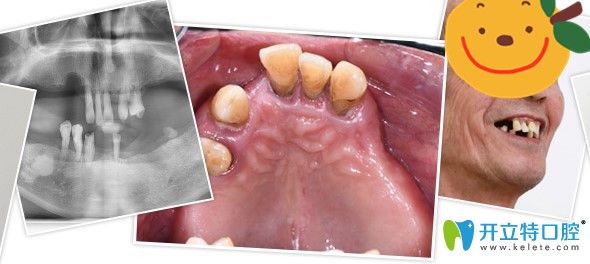

▼郭老全口種植牙前后對(duì)比照

侯國(guó)鎮(zhèn)為郭老做全口種植牙前后對(duì)比照

▼沒(méi)有做種植牙前

沒(méi)有來(lái)廣州廣大口腔做種植牙前

其實(shí)郭老之前剛?cè)毖赖臅r(shí)候做過(guò)活動(dòng)假牙,但是因?yàn)楫愇锔袕?qiáng)烈,并不怎么佩戴,因?yàn)槊撀溲例X周邊沒(méi)有支撐,慢慢的,他的牙齒都逐漸脫落松動(dòng),到他決定做種植牙前,他全口只剩上面5顆牙,下面4顆牙和一顆殘根,而且全都松動(dòng)的很厲害,吃東西嚼不爛,非常痛苦。

根據(jù)侯國(guó)鎮(zhèn)醫(yī)生的建議,郭老做的是all-on-6全口即刻負(fù)重種植牙,全口牙總共種植了12個(gè)種植體,而且種植牙的時(shí)候僅僅花費(fèi)了半個(gè)小時(shí),因?yàn)槭俏?chuàng)手術(shù),術(shù)中出血很少。就他這樣大的年齡,術(shù)后恢復(fù)也是非??焖俚?。

▼種植牙效果圖

郭老全口種植牙效果照片

術(shù)后當(dāng)天就戴上了臨時(shí)牙冠,回家就吃到熱騰騰的飯菜了。時(shí)隔快2年,郭老對(duì)于自己這次種植牙經(jīng)歷從來(lái)沒(méi)有后悔過(guò),只是后悔缺牙后沒(méi)有早早行動(dòng),白白受了多年痛苦。